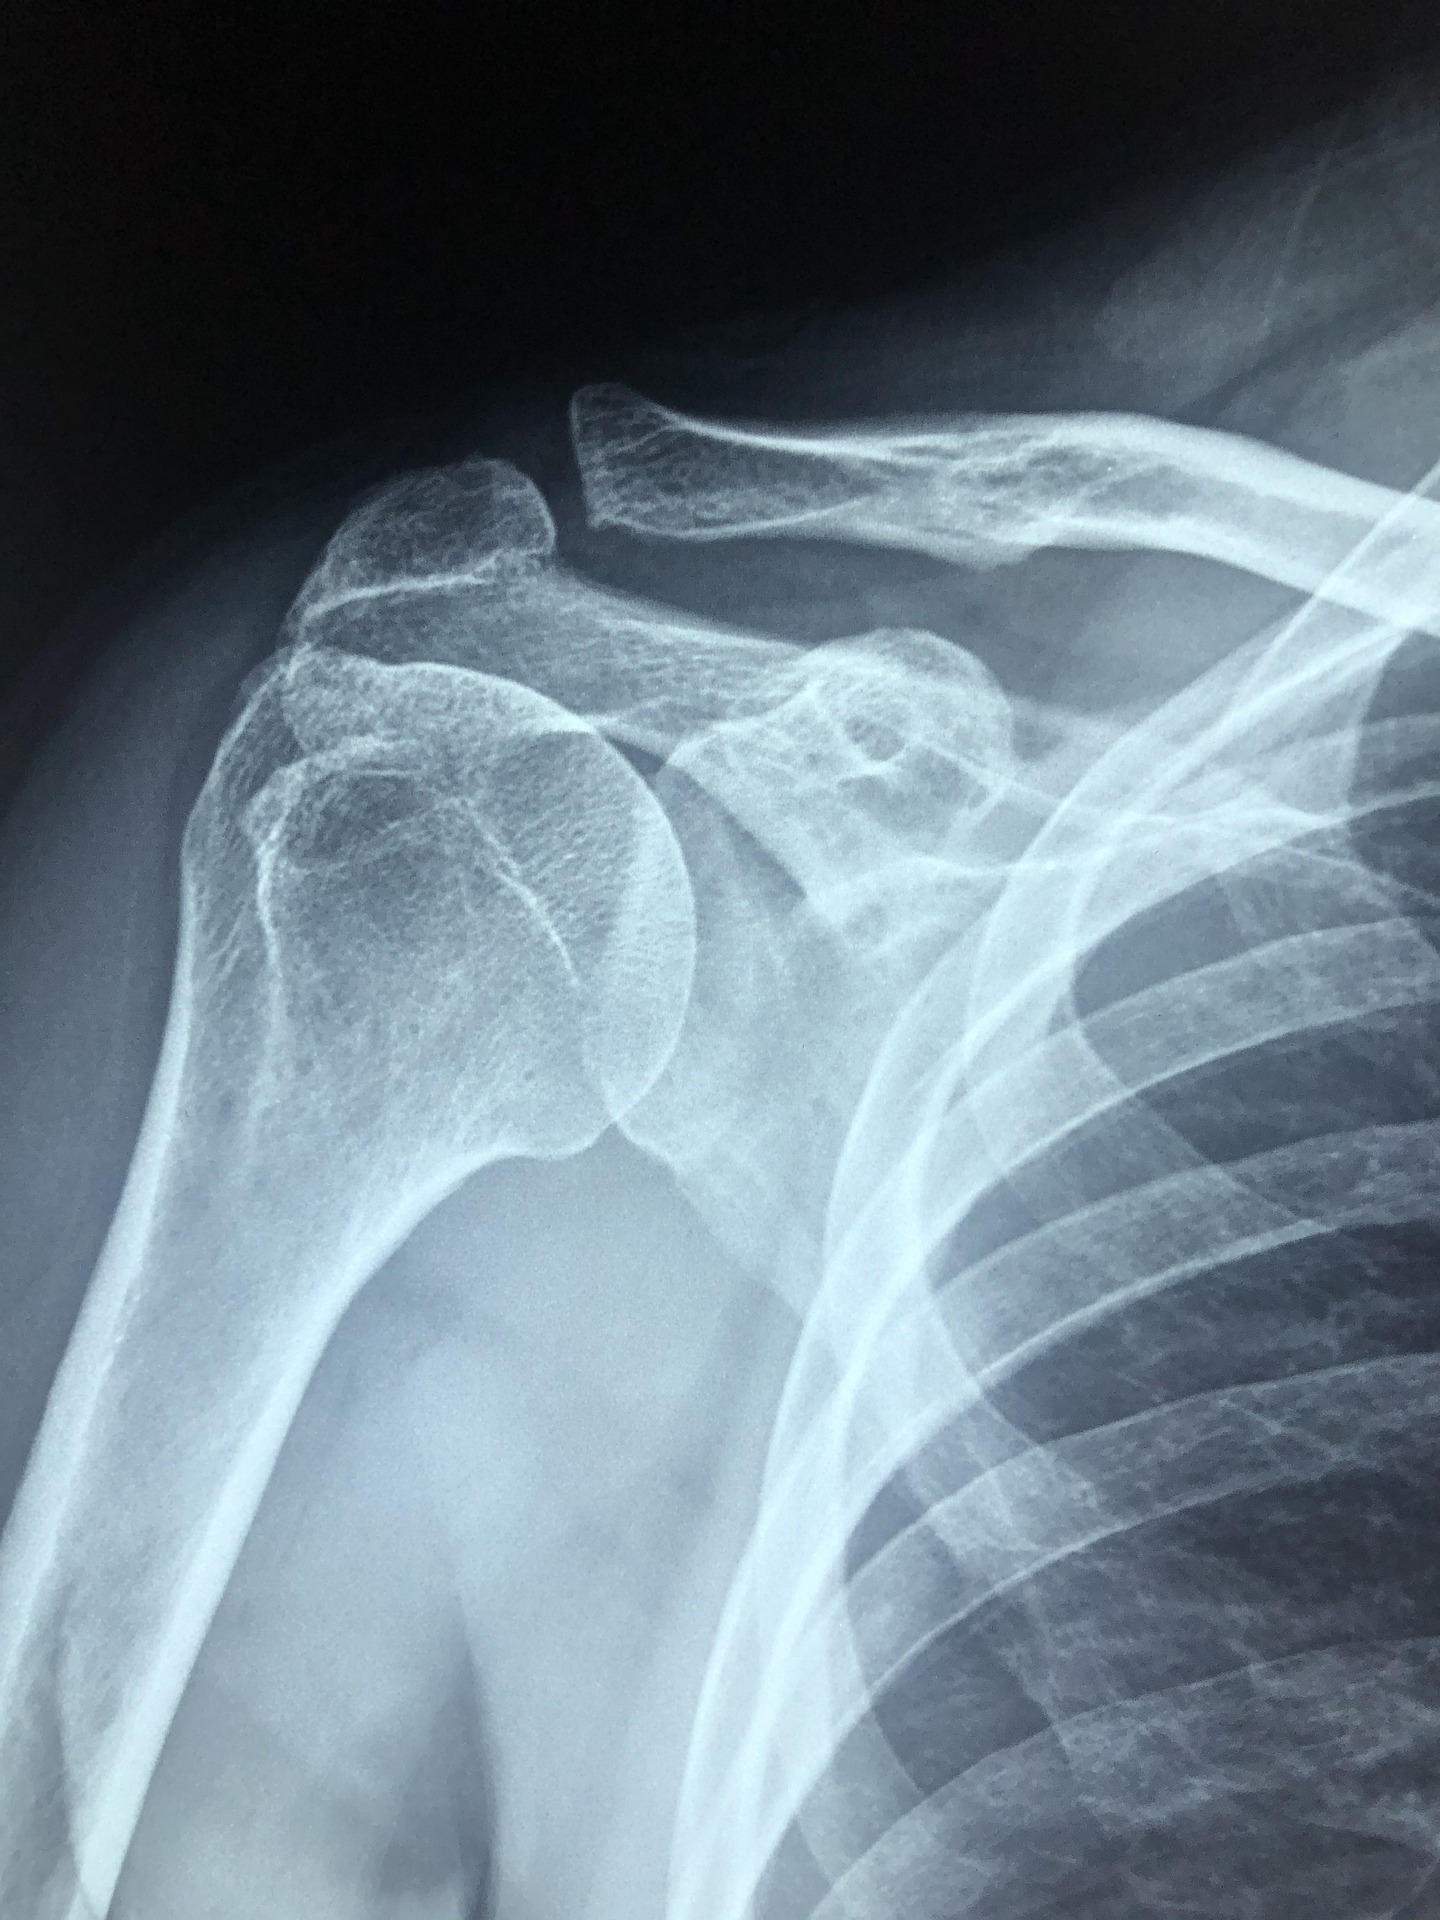

2. 어깨 아픈 사람, 어깨 안 아픈 쪽으로 돌아누워 자기

나이를 먹으면 어깨에 '오십견'이 생기기도 합니다. 오십견은 공식적인 명칭으로 '유착성 관절낭염'이라고 합니다. 팔과 어깨를 잇는 관절 막에 염증이 생기면서 발생하는 질환으로, 팔을 올리면 통증이 느껴지고, 심한 경우 어깨가 굳어져 팔이 아예 올라가지 않을 수 있습니다.

오십견으로 인한 통증은 밤에 특히 심해집니다. 낮에는 팔을 움직이며 어깨를 꾸준히 사용하니 관절과 주변 근육이 굳지 않지만, 움직임이 적은 밤엔 관절이 뻣뻣하게 굳는 탓입니다.

오십견이 있다면 자기 전에 따뜻한 수건으로 어깨를 마사지하는 것이 좋습니다. 이렇게 하면 근육과 관절이 부드러워져 굳지 않도록 도와줍니다. 누울 때의 자세도 중요합니다. 천장을 보고 똑바로 눕기보단 옆으로 누워서 잘 때 통증이 덜합니다. 아프지 않은 쪽 어깨를 바닥에 대고, 쿠션을 가슴에 끼고, 아픈 쪽 팔은 쿠션 위에 올려서 팔이 자

연스레 아래로 늘어지도록 합니다. 이 자세는 팔과 어깨가 수평을 이루어 관절이 수축하는 것을 막아줍니다.